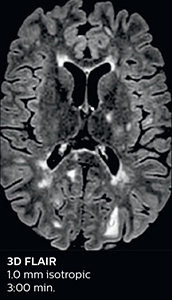

The abbreviated MS protocol for brain is only around 9 minutes, so in case of suspected multiple sclerosis, one or two more advanced sequences may be added, such as PSIR (phase sensitive inversion recovery) or susceptibility-weighted sequences to help us make more confident diagnoses in these inflammatory cases.

“We used to have long examination times for certain types of patients, a few lasting more than 40 minutes,” says Dr. Savatovsky. “What is remarkable, is that now all these examinations are below 30 minutes, which opens up opportunity to add more sequences when needed. It’s really hard to keep a patient for more than 40 minutes in the scanner, but because we have now cut scan times by at least 10 minutes, we can add more sequences without making the exam too long. And this is where the new system helps us make a difference. Examples include our examinations for informing brain tumor classification or giant cell arteritis workup, or for intracranial wall imaging – so in patients where we need several advanced sequences or high resolution sequences.” “We added three additional sequences in our brain neoplasm classification exam: a 3D SWI sequence, APT and ASL on top of 3D morphologic sequences, an isotropic DSC (dynamic susceptibility contrast) and multivoxel spectroscopy. I think that in patients that need a classification for brain mass, for example, we can provide a more detailed and confident diagnosis than before, allowing the clinicians to decide for either a medical workup if no tumor is suspected, or for neurosurgery as soon as possible if a neoplasm is suspected.” “In multiple sclerosis patients, we increasingly include a multishot susceptibility sequence [3] in our routine cases, thanks to the shorter scan times. Our abbreviated MS protocol for brain is around 8 to 9 minutes, so we can ask for one or two additional sequences to visualize the central veins, or to get an additional contrast to better depict posterior fossa lesions. In cases of white matter lesions of unknown significance on FLAIR images, for example when we see high signal hyperintensities in the brain, we can add on more advanced sequences such as PSIR (phase sensitive inversion recovery) or susceptibility-weighted sequences to help us in distinguishing between MS and nonspecific or vascular abnormalities in these inflammatory cases.”